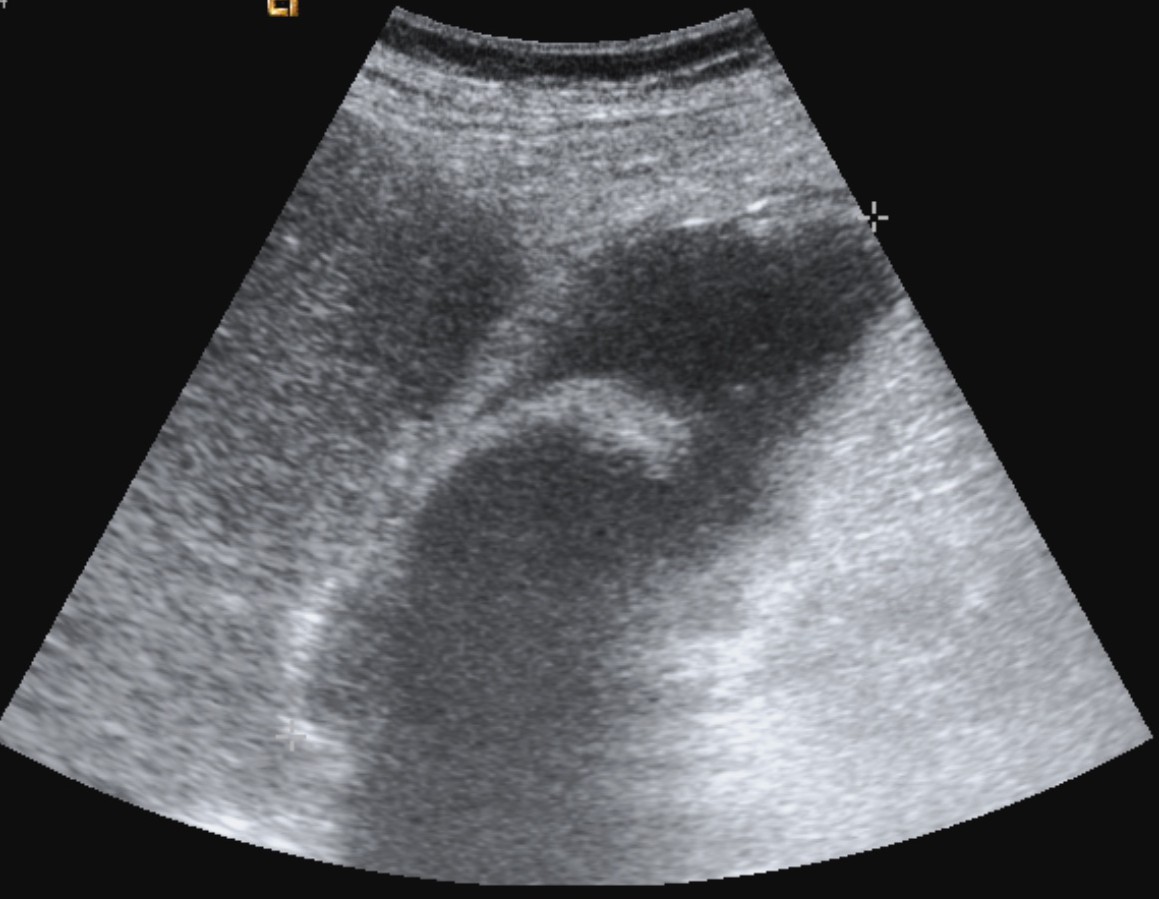

Se realiza ecografía abdominal:

En sucesivos cortes observamos lo siguiente:

Se observa una mala evolución radiológica. Dada la clínica del paciente y los hallazgos ecográficos podemos concluir que estos hallazgos son compatibles una colecistitis xantunogranulomatosa litiásica sobreinfectada (que se confirmó posteriormente con anatomía patológica).